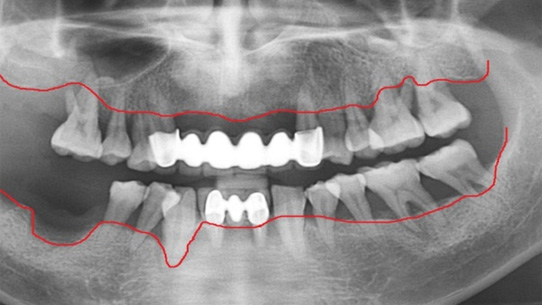

치주염은 성인 70%가 가지고 있는 정도로 흔한데 자각증세가 없이 진행되다 심해졌을 때 잇몸이 붓고 피가 나고 흔들리는 증세가 나타납니다.

적절한 시기에 치주치료를 하지 않으면 잇몸 뼈의 흡수로 인하여 방치하면 발치까지 이어지게 됩니다.

뿌리에 염증으로 흔들리는 치아

치주 치료로 재생된 건강한 잇몸

치주염은 잇몸의 뼈 부분까지 염증이 진행된 상태를 말합니다. 치석이 치주염 상태가 될 때까지, 즉, 치아 뿌리까지 들러붙어 내려가게 되면

치주인대가 소실되고 치조골까지 녹아 내리게 됩니다. 고운미소에서는 임플란트를 하기 전에 치주치료, 큐렛, 근관치료, 치근단 수술,

치아 재식술등의 다양한 치료로 치아를 최대한 살리려고 노력하고 있습니다.